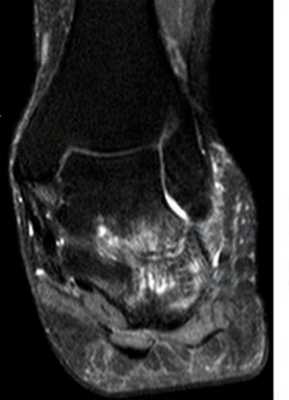

Пациент М. 1980 г.р., травму получил при падении на стопы с высоты 1,5 метра. Лечился по месту жительства (в травмпункте районной больницы) консервативно в гипсовой повязке в течение 14 дней. Консультирован в травматологическом отделении ФГБУ «УНИИТО им. В.Д. Чаклина» Минздрава РФ, предложено оперативное лечение. При поступлении кожные покровы стопы чистые, без признаков воспаления и сдавления тканей. Стопа отечна, уплощена. На рис. 1 представлены рентгенограммы пациента. Прооперирован через 2 недели после травмы. Операция состоит из двух этапов. Первый этап заключается в наложении дистракционного аппарата. Проводятся две спицы 1,8 мм во фронтальной плоскости: первая через нижнюю треть диафиза большеберцовой кости, вторая через бугор пяточной кости (рис. 2). Спицы фиксируются в дистракционном аппарате, выполненном из двух полуколец, соединенных между собой двумя телескопическими тягами. Особое расположение полуколец, фиксация спиц на концах полуколец, крепление кронштейнов для телескопических тяг обеспечивает тракцию пяточной кости в необходимом направлении с использованием минимального количества спиц и внешних опор при сохранении необходимого поля обзора для проведения рентгенологического и визуального контроля репозиции и фиксации. Второй этап - закрытая элевация импрессированной суставной поверхности и окончательная репозиция пяточной кости. Через разрез длиной до 1 см по латеральному краю ахиллова сухожилия (рис. 3) в месте его прикрепления к пяточной кости под соответствующий фрагмент подводится элеватор (рис. 4), манипуляцией которым устраняется смещение и выполняется провизорная фиксация спицами 1,5 мм (рис. 5). При сагиттальном раскалывании суставной фасетки целесообразно проведение одного-двух винтов субхондрально (рис. 6). Стержень вводится с дорзальной поверхности пяточной кости по ее оси через разрез до 2 см по предварительно сформированному остеотомом каналу (рис. 7, 8). Далее через проколы кожи с помощью кондуктора (рис. 9) выполняется запирание винтами с латеральной поверхности, внешнее устройство демонтируется. Достигнуто удовлетворительное стояние отломков (рис. 10).

Рис. 7. По оси пятки проводится спица, по которой затем канюлированным сверлом формируется канал для введения стержня

Рис. 8. Вводится стержень на кондукторе. Данная иллюстрация показывает, что компоновка аппарата внешней фиксации не создает помех для кондуктора